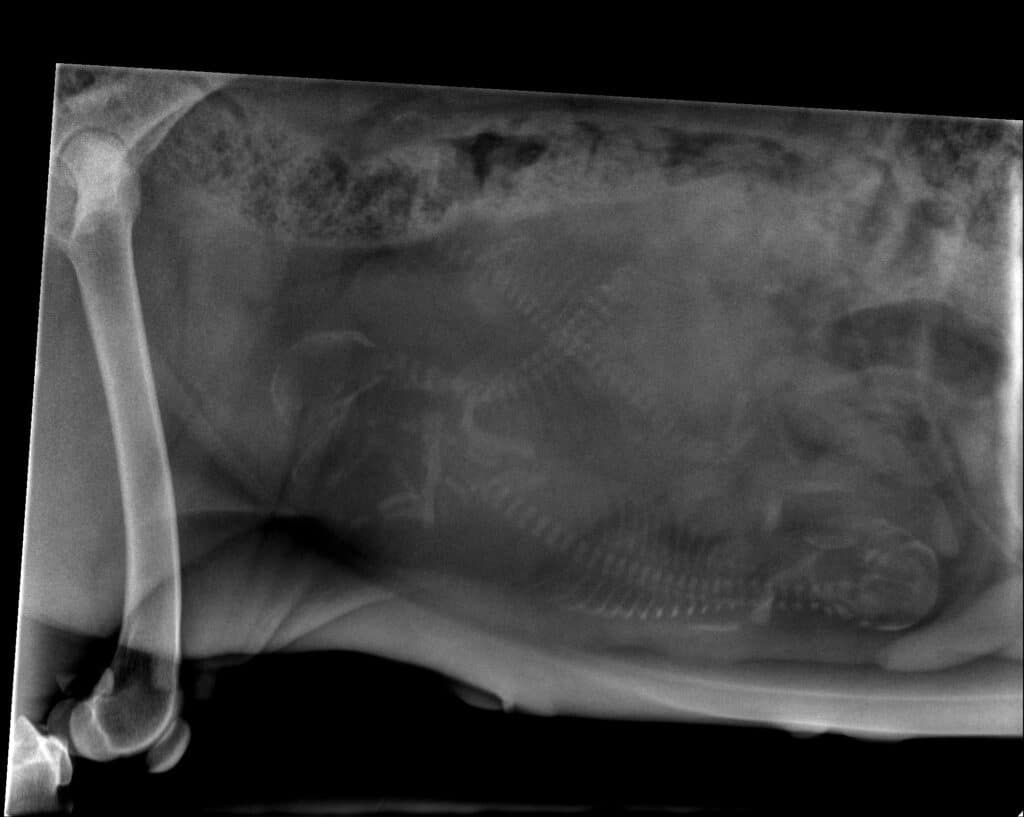

Radiographie de l'abdomen d'un lapin qui ne mange plus. Il y a une importante accumulation de gaz dans les intestins.